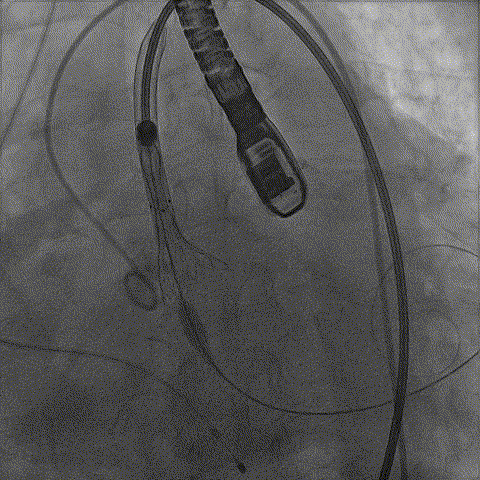

手术影像:

瓣膜依次缓慢脱钩

完全释放后造影无漏